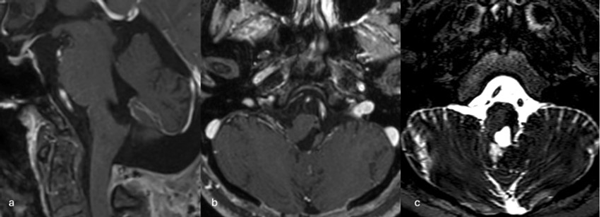

Figura 2. RM postquirúrgica de encéfalo. Se evidencia una exéresis completa, sin lesión de estructuras adyacentes. A) Imagen ponderada en T1 posterior a la administración de gadolinio, corte axial. B) Imagen ponderada en T2, corte axial.

Figura 5. RM postquirúrgica de encéfalo. Se evidencia una exéresis completa con hiperintensidad en T2 en regresión. A, B y C) Imágenes ponderadas en T2 en cortes coronal, axial y sagital, respectivamente.

Figura 8. RM postquirúrgica de encéfalo. Se evidencia una exéresis completa, sin daño del parénquima adyacente. A, B y C) Imágenes ponderadas en T2 en cortes coronal, axial y sagital, respectivamente.

Figura 9. RM preoperatoria de encéfalo. Se evidencia una lesión única intraaxial bulbotrigonal izquierda, que contacta la mitad inferior del piso del cuarto ventrículo, hiperintensa en T1 y T2, con vacíos de flujo que impresionan provenir de una malformación del desarrollo venoso, lo que sugiere una malformación cavernomatosa. A) Imagen en corte sagital ponderada en T1 posterior a la administración de gadolinio. B y C) Imágenes en corte axial ponderadas en T1 y T2, respectivamente.

Figura 11. RM postquirúrgica de encéfalo. Se evidencia una exéresis completa, sin daño del parénquima adyacente. A) Imagen en corte sagital ponderada en T1 posterior a la administración de gadolinio. B y C) Imágenes en corte axial ponderadas en T1 posterior a la administración de gadolinio y T2, respectivamente.